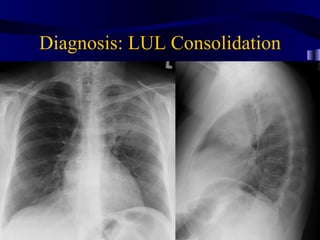

Lul consolidation

Diagnosis: LUL Consolidation